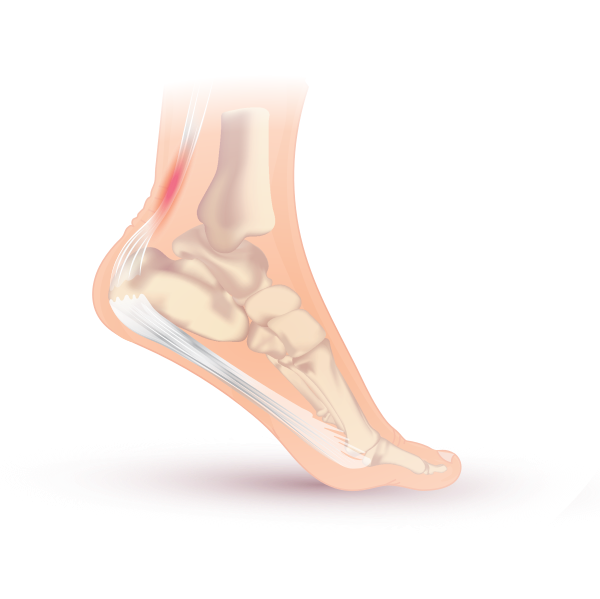

Тендинит ахиллова сухожилия (ахиллова тендинопатия, ахиллотендинит) — это заболевание ахиллова сухожилия, сопровождающееся изменениями в структуре и механических свойствах сухожилия. Наиболее распространёнными симптомами являются боль и припухлость в области задней поверхности лодыжки. Обычно боль усиливается в начале тренировки и уменьшается после неё. Также может наблюдаться скованность в голеностопном суставе. Это заболевание может возникнуть у людей, ведущих активный образ жизни, включая спортсменов, а также у тех, кто предпочитает сидячий образ жизни. В результате ахилловой тендинопатии могут возникнуть серьёзные нарушения ходьбы и бега[1].

Гистопатологические исследования показали, что тендинит ахиллова сухожилия является результатом неадекватной реакции заживления и сопутствующей неоваскуляризации, приводящей к дегенеративным изменениям сухожилия. Кроме того, в случаях инсерционной ахиллопатии часто сопутствуют многочисленные дополнительные нарушения, такие как кальцификация сухожилия, воспаление ретрокалькулярной сумки и тендиноз, а также разрастание костей, известное как деформация Хаглунда[16].

Повреждения ахиллова сухожилия можно разделить на инсерционную тендинопатию (20-25 % травм), тендинопатию средней части (55-65 %) и повреждения проксимального мышечно-сухожильного соединения (9-25 %) в зависимости от локализации боли[21].